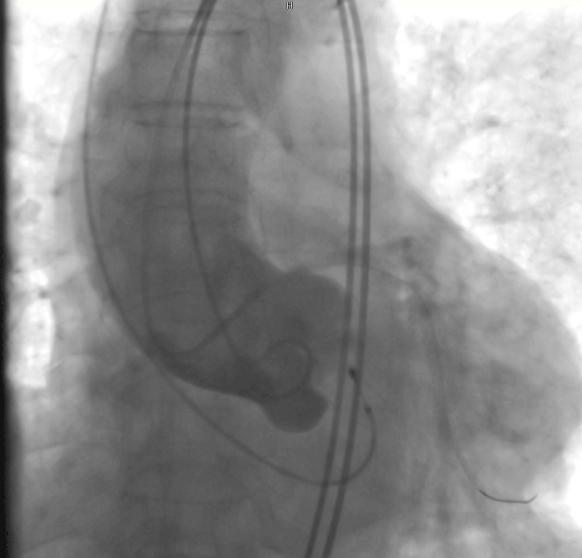

术中,在DSA(数字减影血管造影)严密实时监测下,何晋主任医师从杨爷爷大腿根部股动脉穿刺,通过大血管将主动脉支架瓣膜及装置输送到病变的主动脉瓣位置,缓缓释放支架瓣膜,经过精密调控,支架瓣膜精确植入,原先狭窄的瓣膜口子一下就开通了,术中监测主动脉瓣和心室压差为零。

术后第二天,杨爷爷就可以下地走路,胸闷、气促明显好转,4月25日顺利出院。“以后我还可以出去旅游,享享儿女福。”出院前,杨爷爷一再向医护团队表示感谢。